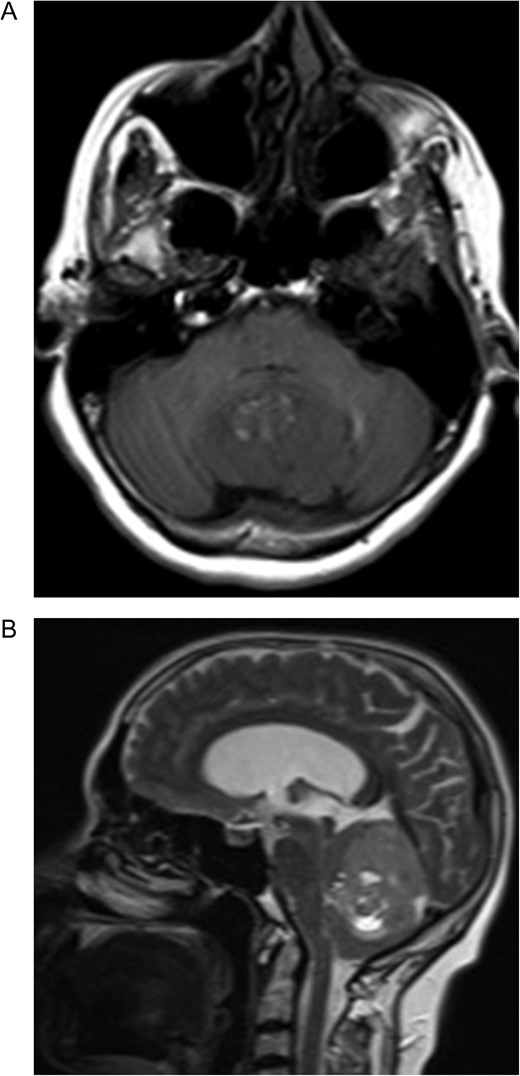

A 55-year-old woman presented with headache, dizziness and gait imbalance for 2 months. Patient’s history revealed a posterior fossa tumor that had been diagnosed 4 years ago prior to admission to our clinic. At that time, contrast enhanced of magnetic resonance imaging (MRI)showed the ill defined lesion, 5.5×3.5×4 cm in size without perilesional edema (Fig. 1A,B). During this 4 years period, her follow-up had been performed with serial MRI (Fig. 2A and B) and CT assessments (Fig. 3). Until 2 months ago, she had only intermittent headache. On neurological examination, she had cerebellar signs including ataxia and also bilateral papilledema through ocular investigations. CT assessment showed punctate calcified lesion demonstrated with undifferentiated margins of the lesion from the cerebellar parenchyma. The last MRI findings showed heterogeneous ill defined lesion without perilesional edema in vermis and extending to the adjoining cerebellar hemisphere at the supracerebellar infratentorial space with a dimension of 6.7×4×4 cm size causing compression of the fourth ventricle and marked hydrocephalous. The patient underwent surgery through a midline supracerebellar infratentorial approach in the prone position. It was a soft whitish intra-axial tumor, moderately vascular with a good plane between the vermis and cerebellum. A complete resection was achieved. The cerebrospinal fluid shunt was not decided to be placed (Fig. 4). Pathological diagnosis was reported as CLN. Immunohistochemical study, synaptophysin and neuron-specific enolase (NSE) immunopositivity were found (Fig. 5). In the mean time, glial fibrillary acidic protein (GFAP) was immunonegative and Ki-67 index was 2%. After operation, she had uneventful postoperative period and was discharged on seventh day.

Preoperative MRI (A) Axial T1-weighted MRI showing hypointense lesion located in the cerebellar vermis. Note the hyperintense area corresponding to the fat component. (B) The lesion is hyperintense and well circumscribed on sagittal T2-weighted MRI. Note the supratentorial hydrocephalus secondary to compression of the fourth ventricule.